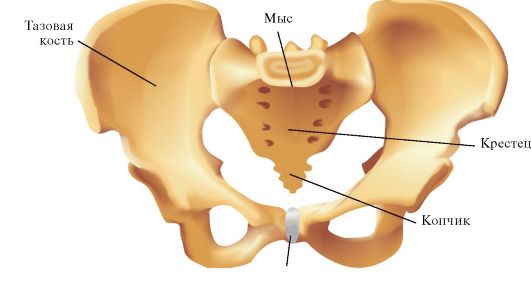

Анатомия малого таза: детальные схемы и изображения